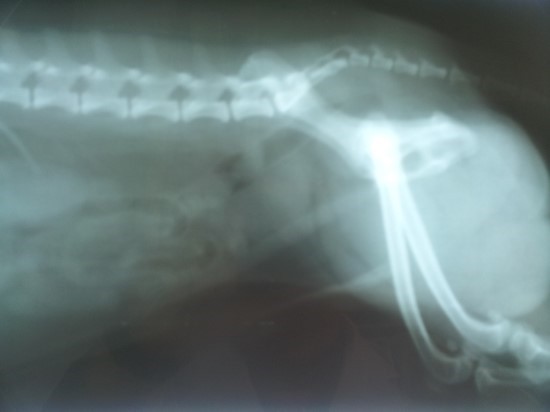

남자의 건강을 위협하는 대표 질병 중 한 가지는 전립선 질병이다. 전립선염은 남자의 50%가 일생에 한 번은 겪어볼 정도로 흔한 질병이 됐으며, 전립선암은 최근 20년간 20배 넘게 증가할 정도로 대중적인 질환이 되었는데요.